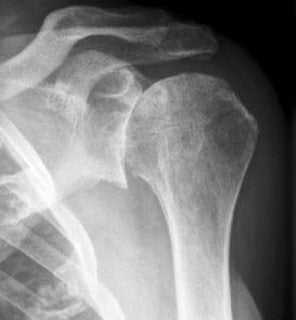

Рентгенография для обнаружения костных наростов, сужения суставной щели и других деформаций.

На рентгенографических снимках заметно нечетное сужение суставной щели, приводящее к уменьшению подвижности плеча. На этой стадии появляются единичные остеофиты на краях суставных плоскостей. Возникают и первые болезненные ощущения после подъема тяжестей, выполнения монотонных движений, переохлаждения.

При остеоартрозе плеча 3 степени тяжести интенсивность болезненности усиливается, снижается объем движений, а при сгибании или разгибании сустава, отведении руки за спину отчетливо слышатся щелчки. На рентгенограммах обнаруживаются множественные костные наросты, субхондральный остеосклероз, заметное сужение суставной щели.

На этой стадии сустав сильно деформирован, а его подвижность резко ограничена. Суставная щель практически полностью отсутствует. На снимках отчетливо визуализируются субхондральные кисты (полости с полужидким содержимым), обширные остеофиты. При заболевании 4 степени в суставе свободно перемещаются кусочки разрушенного хряща. Если они попадают между костными поверхностями, то образуется суставная «мышь», а плечо блокируется.

Выявление патологии

Наиболее информативна при остеоартрозе плечевого сустава рентгенография. По характерным рентгенографическим признакам можно выявить не только само заболевание, но и его стадию и особенности течения. При подозрении на воспаление тканей, а также для более детального изучения состояния сустава проводится МРТ, КТ. Выполнение артроскопии позволяет сделать прицельный забор биологических образцов:

Деформирующий артроз плечевого сустава 1 степени на рентгенограмме практически незаметен. Иногда удается установить небольшое сужение суставной щели. Однако при более серьезном обследовании – КТ или МРТ, поражение костно-хрящевой структуры четко заметно. Видны начальные деформации суставных поверхностей, отек подлежащих мягких тканей, небольшая узурация.

Деформирующий артроз плечевого сустава 2 степени проявляется уже значительными изменениями. Их можно представить так:

- резкое сужение суставной щели;

- деструкция суставных поверхностей; – костные разрастания;

- дефицит хрящевой прослойки;

- грубая узурация костных структур;

- остеопорозные изменения плечевой кости.